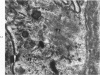

Liver biopsies obtained from 24 patients with alcoholic liver disease were studied by light and electron microscopy. Comparisons of the same cells in adjacent sections revealed that alcoholic hyalin is a fibrillar deposit without limiting membranes and is readily distinguished from giant mitochondria. This characteristic fibrillar structure was encountered in hepatocytes, ductular cells and in benign and malignant hepatomas. Three distinct morphologic forms of alcoholic hyalin were observed: a) bundles of filaments in parallel arrays, b) clusters of randomly oriented fibrils and c) a granular or amorphous substance containing only scattered remains of fibrils. Closely associated with alcoholic hyalin and often found along its entire circumference, were bundles of fine filaments in parallel arrangement of much smaller size. These occasionally displayed variations in orientation and merged with the filaments in the alcoholic hyalin body. Similar fine filaments were observed, in considerable excess, in cells which did not contain alcoholic hyalin. According to our findings, the fine filaments and the significantly larger filaments in alcoholic hyalin could be parts of a contractile system elaborated by host cells during the course of hepatic injury.